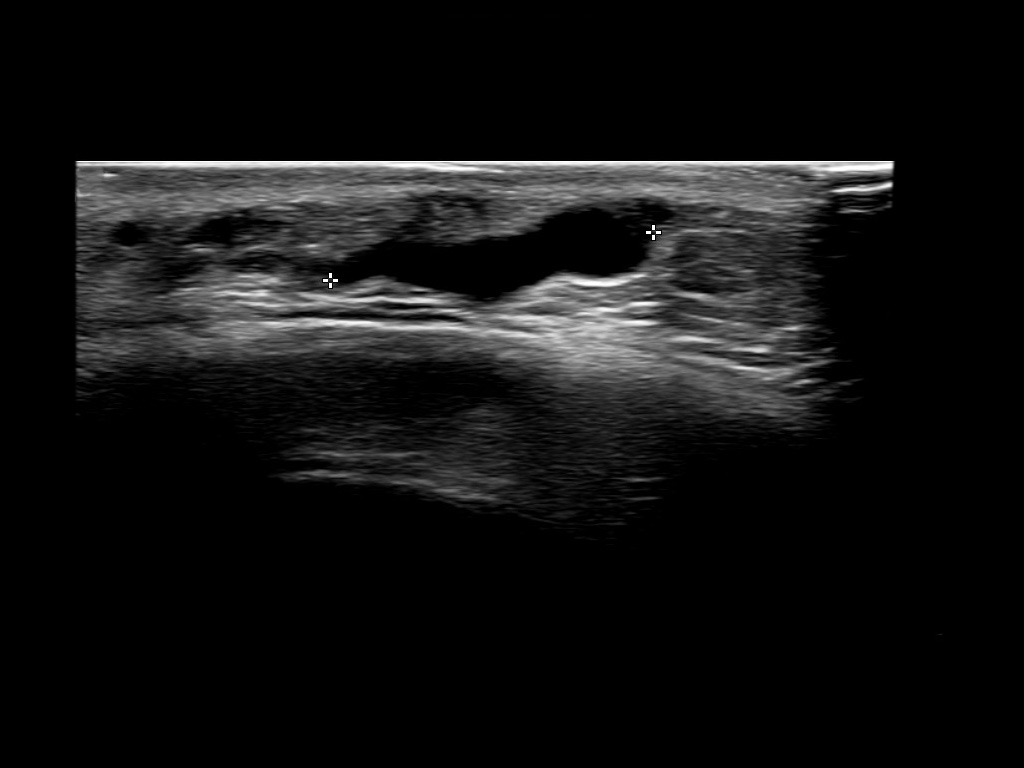

Fascia

Filler deposits may end up unintentionally in the SMAS or fascial layers of the skin. Very often this will not lead to adverse events, however, adverse events ( nodules, migration / redistribution impaired muscle movement and smiling and malar edema) are are often related to filler ending up in the SMAS or fascia.

Study the first image to recognize the different layers. If you are sure about the layers, swipe to the second image to view the answer (if applicable).